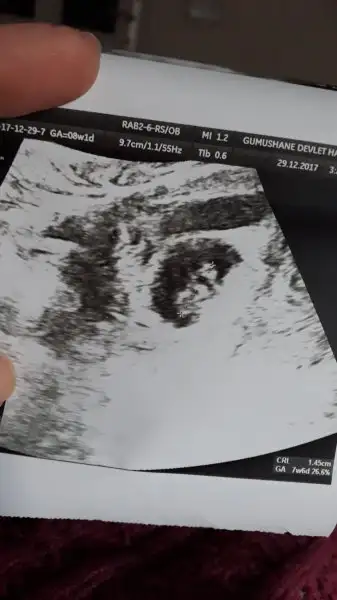

Banada yorum yapsanız arkadaşlar . 8 haftalık karından ultrason

Eklentiler

• IMG_20171225173946.webp

IMG_20171225173946.webp

11,5 KB · Görüntüleme: 169